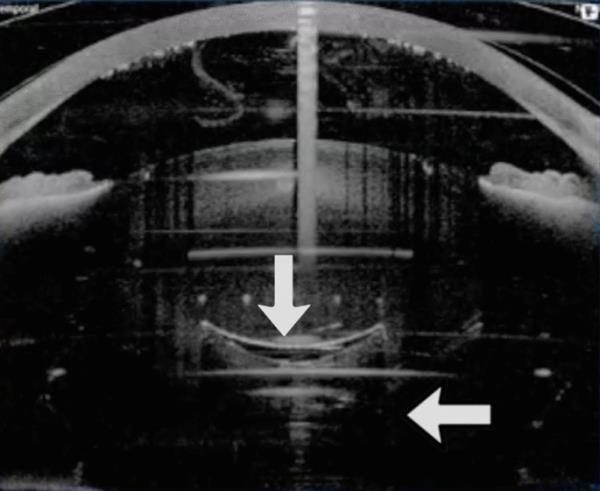

囊膜切开后眼倾斜,此时碎片量已经设定。这导致后囊部分被飞秒激光切割

FLACS期间后囊的一些运动是正常的。(箭头表示后囊和飞秒激光产生的微泡。)另见补充资料中的视频2